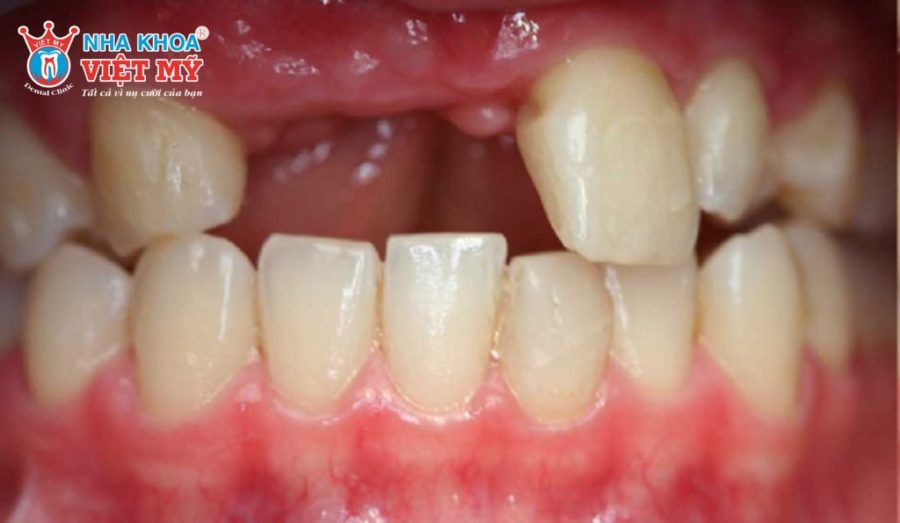

- Tiêu xương hàm sau nhổ răng lâu ngày.

Chuyên gia nhấn mạnh việc trồng Implant càng sớm càng tốt để ngăn ngừa tiêu xương hàm, đồng thời đảm bảo chức năng ăn nhai, thẩm mỹ khuôn mặt và sức khỏe tổng thể.

- Ổ răng đã lành thương cơ bản, mô nướu ổn định.

- Xương hàm chưa bị tiêu nhiều, dễ dàng đặt trụ Implant với độ vững chắc cao.